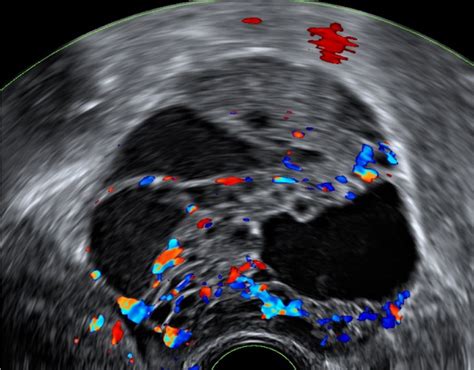

Ultrazvočni pregled, tako v 2D kot 3D tehniki, omogoča podroben vpogled v strukturo maternice in jajčnikov. Z njim lahko ocenimo prirojene in pridobljene nepravilnosti, kot so nepravilnosti maternične votline ali ciste na jajčnikih. Poseben poudarek je na preštevanju antralnih foliklov (AFC) v jajčnikih, ki predstavljajo pomemben pokazatelj ovarijske rezerve oziroma preostalega števila jajčec.

Sonohisterografija je naprednejša ultrazvočna metoda, pri kateri se v votlino maternice prek tankega katetra vbrizga sterilna fiziološka raztopina. Ta postopek omogoča natančnejši prikaz sluznice maternice in odkrivanje morebitnih nepravilnosti, kot so polipi ali manjše nepravilnosti, ki bi sicer ostale skrite.

Histerosalpingo kontrastna sonografija (HyCoSy)

HyCoSy je diagnostična metoda, ki omogoča oceno prehodnosti jajcevodov in oblike maternične votline. Med postopkom se skozi tanki kateter, vstavljen v maternično votlino, vbrizga poseben kontrastno sredstvo. Če sta jajcevoda prehodna, se kontrastno sredstvo preko njiju izlije v trebušno votlino in oblije jajčnike. V primeru zapore jajcevodov pa z ultrazvokom vidimo natančno mesto zapore. Prednost ultrazvočne metode je, da ne izpostavlja žensk rentgenskim žarkom, kontrastno sredstvo pa je varno za morebitni zgodnji razvoj zarodka.